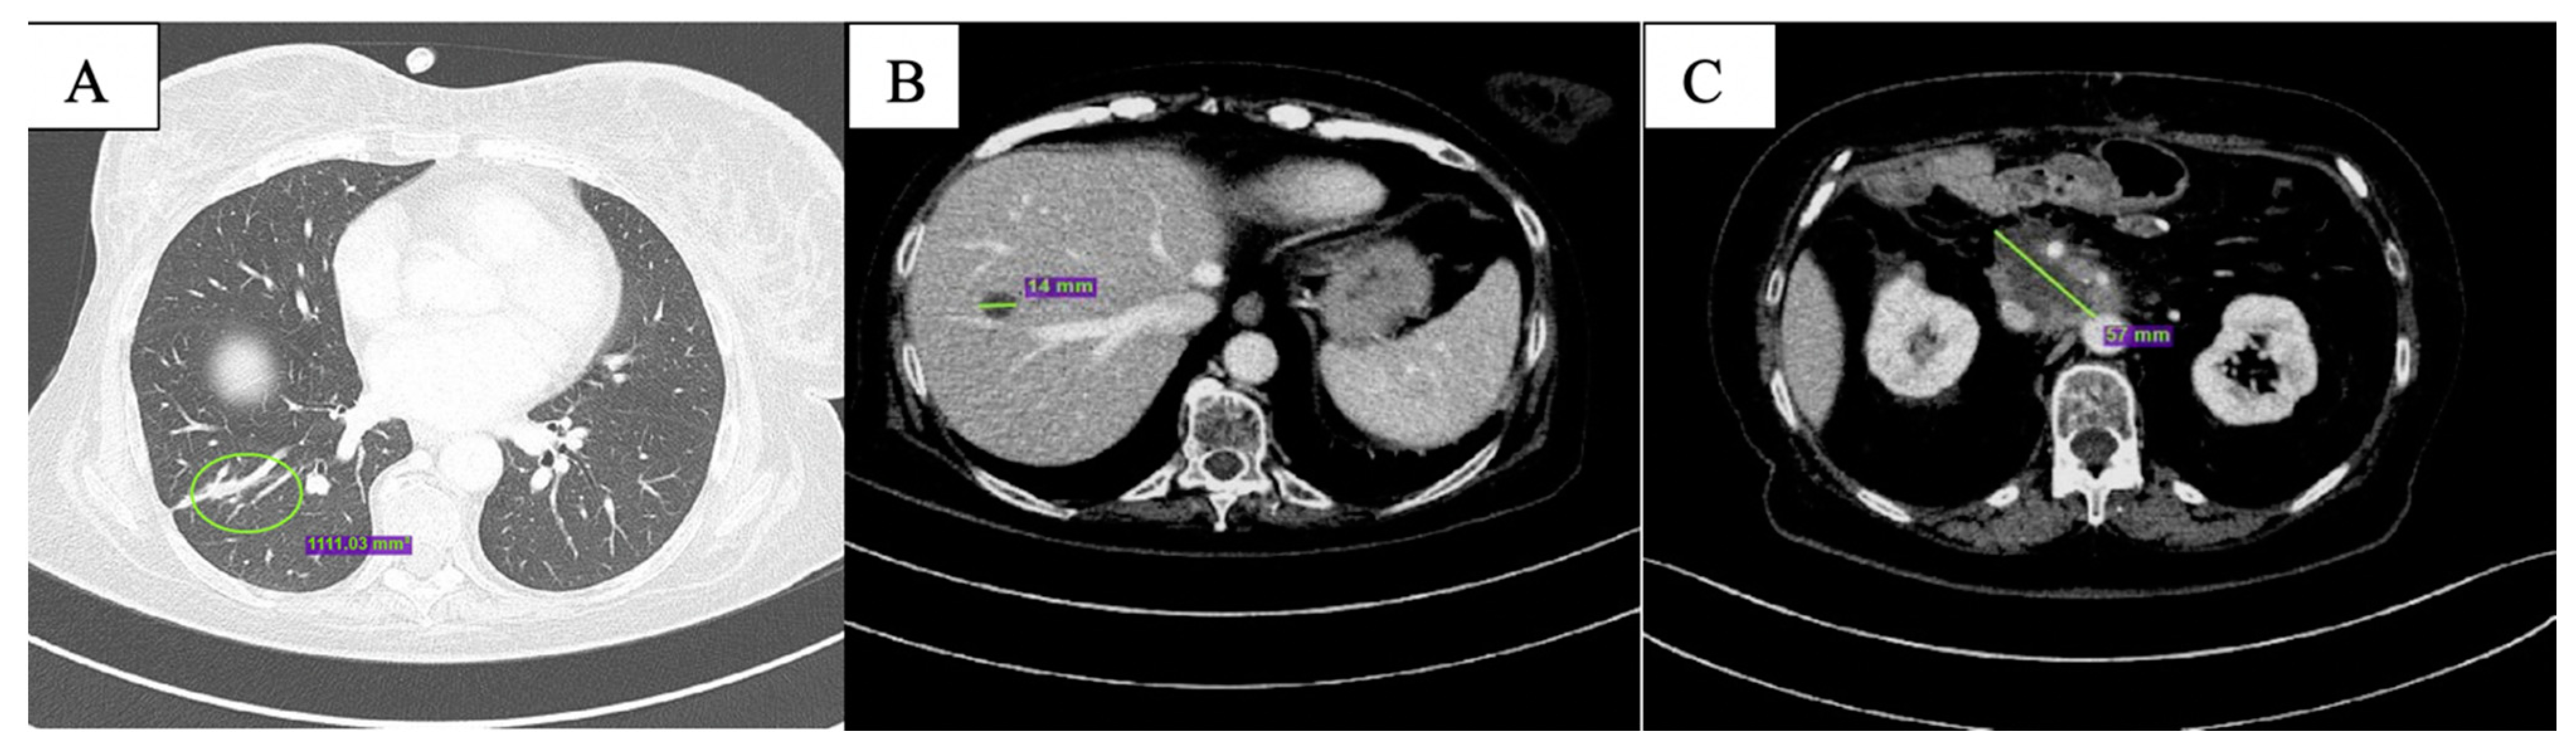

After the first two months of therapy, the patient displayed complete response on the lung metastases (Figure 2A); overall, partial response was documented (Figure 2B,C). One single new liver lesion of uncertain origin was documented. After staff consultation, considering the good clinical conditions, the absence of toxicities from treatment, except for G1 nausea per CTCAE v. 5.0 [13], the diameter of the new lesion (<10 mm), and the excellent response obtained on the other lesions, we decided to continue with the same therapy.

Figure 2.

CT scan after the first 2 months of olaparib showing complete response of the nodular lesion in inferior lobe of the right lung (A), reduction in size of the hepatic lesion in the 8th segment (B) and of peripancreatic tissue (C).